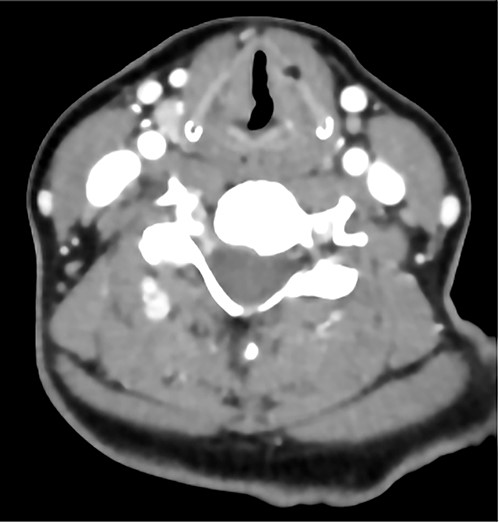

The patient maintained good oxygen saturation levels in room air with no signs of respiratory distress. She had a hoarse voice with a maximum phonation time of 10 s. Neck examination was unremarkable. Bedside transnasal flexible endoscope revealed bilateral vocal folds movement with polypoid lesions involving the middle two-thirds of the right vocal fold and the posterior part of the left vocal fold with edematous interarytenoid mucosa. Moreover, polypoid lesions were also seen in the base of tongue, epiglottis, with cobblestoning of the posterior pharyngeal wall (Figs 1 and 2). Basic laboratory tests were within the normal range. A contrasted neck computed tomography (CT) scan revealed bilateral asymmetric thickening of the vocal folds with medialization of the right vocal fold, with no enlarged cervical lymph nodes (Fig. 3).

A contrasted neck CT scan showing bilateral asymmetric thickening of the vocal folds with medialization of the right vocal fold.